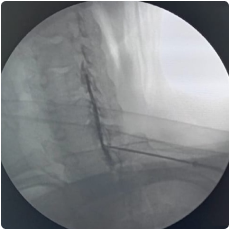

image 912

Intraop fluoroscopy image of needle placement at the cervical facet